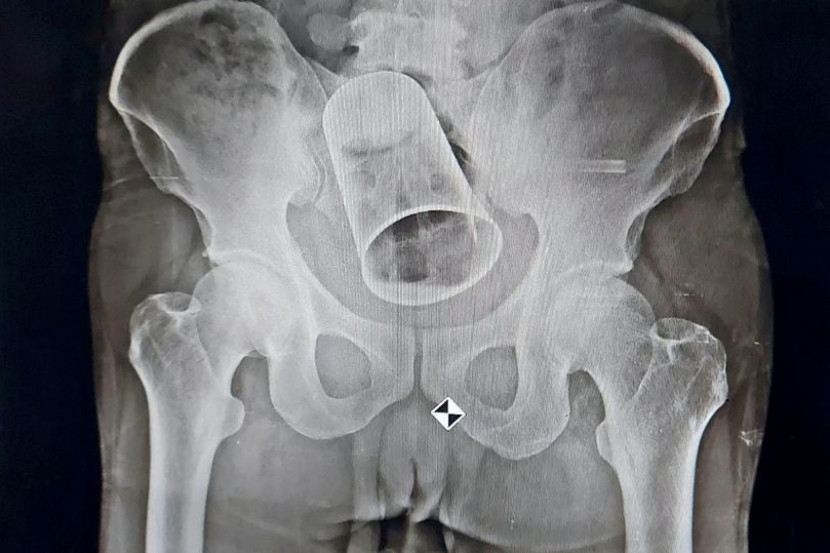

Imbasan X-ray yang dilakukan di Kolej Perubatan dan Hospital MKCG di bandar Berhampur mendapati cawan itu tersangkut di dalam usus.

Doktor cuba mengambil semula cawan tersebut melalui rektum tetapi percubaan mereka tidak berjaya.

Pembedahan dilakukan melibatkan pemotongan usus sebelum berjaya mengeluarkan gelas dari dubur pesakit.